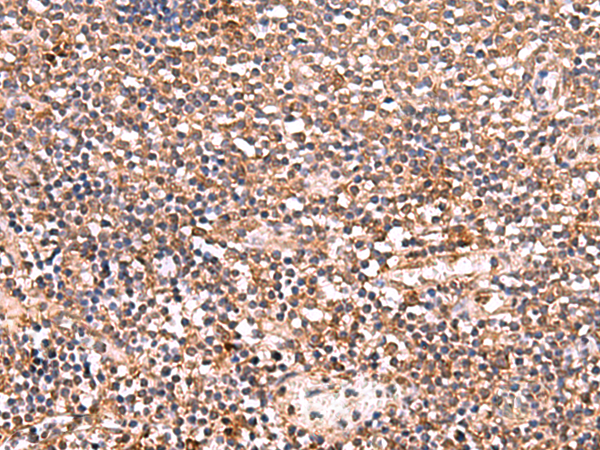

分类: 科研抗体货号: P00563别名: NGFB; HSAN5; Beta-NGF应用: IHC反应种属: Human, Mouse, Rat